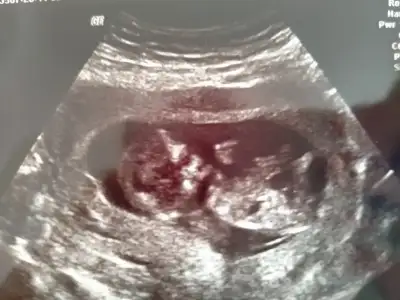

Nubu yüksek görünüyor sanki net değil karışık görünüyor emin olamadimBaşka usg yok doktor kıza benziyor demisti ama net değil demisti

Canım 11 de büyük olasılık kız 12 de nubu kalktı kız da olabilir erkek de dedi. 15 te %100 kız dedi 16 da hala kız dediSize 12.haftada doktor, erkek mi dedi?

Kız gibi sanki kaç haftalık usgler 11 12 13 haftalar olmalı

12 haftalıkKız gibi sanki kaç haftalık usgler 11 12 13 haftalar olmalı

Emin olamadım başka USG varsa paylaşın sanki erkek gibi gibi ama emin değilimMerhaba 11+0 tahminde bulunur musunuz?

Birde bu var :)Emin olamadım başka USG varsa paylaşın sanki erkek gibi gibi ama emin değilim

Net değil olursa 12 13 haftalar paylasirsinBirde bu var :)

Merhaba tahmininiz doğru çıktı doktorumuz %95 kız dediDr tam -----+ nubtan geçmiş ölçümü emin değilim sanki kız 11 12 13 haftalar olursa paylasin